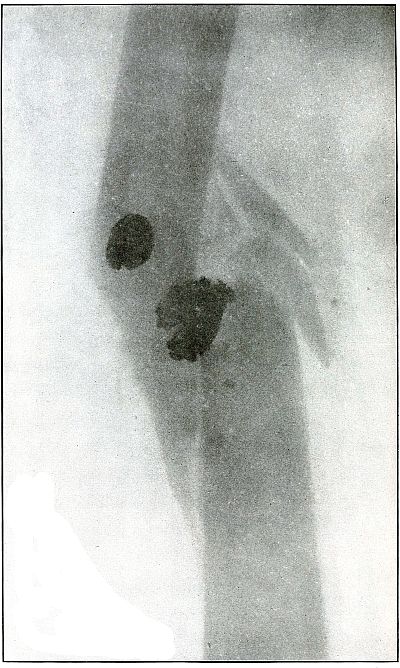

Plate 14.

_

[Pg 39]

Rifle—Plate 14.

UPPER EXTREMITY.

Gunshot Fracture of the Humerus,

with Lodgment of the Missile.

The missile was a fragment of a ricocheted rifle ball, with a part of the lead core carried in a portion of the jacket. The course was from before, backward, striking the humerus in lower third, and leaving particles of lead along its trade.

The wound was only slightly infected. Several detached fragments of bone have been removed.

The treatment in such cases is conservative, with management of the infection and without formal search for the projectile.

The results in such cases are favorable with some shortening of the bone. [Pg 40]